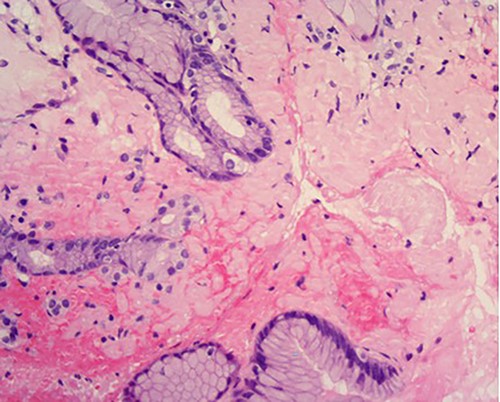

A 76-year-old lady presented to the outpatient clinic with a history of lower abdominal bloating and lethargy for 1 week. The patient denied abdominal pain, nausea, altered bowel habits or GI bleeding. Her past medical history included gastroesophageal reflux disease, ulcerative colitis and a previous hysterectomy. Physical examination exhibited pallor of the conjunctiva, distended abdomen with visible peristalsis on inspection but soft, non-tender on palpation and absence of ascites. Laboratory testing found normocytic normochromic anaemia, thrombocytosis and a positive myeloma screen with elevated kappa to lambda free light chain ratio despite normal renal and liver function. An ultrasound of the abdomen was unremarkable. Computed tomography (CT) with IV contrast of the abdomen revealed diffuse thickening of the small and large bowel with the small bowel dilated throughout. Magnetic resonance imaging of the small bowel showed multiple abnormally thickened loops of the jejunum and proximal ileum with a maximal wall thickness of 0.9 cm (Figs 1 and 2). Gastroscopy revealed severe distal oesophagitis, the stomach contained patchy telangiectasia and gastritis with sloughy mucosa at the incisura in addition to duodenitis with stricture at the second part of duodenum (D2) (Figs 3 and 4). Histopathology from the biopsies of the gastric incisura, D2 and the proximal jejunum displayed reactive changes with intramucosal haemorrhage and extensive deposition of pink amorphous, eosinophilic material on haematoxylin & eosin (H&E) stain. The deposits were predominantly seen in the proximal jejunum with a positive Congo red stain showing apple-green birefringence under polarized light (Figs 5 and 6). The patient was referred to Haematology, and a bone marrow aspirate and trephine biopsy revealed proliferation of 15% mature plasma cells consistent with the diagnosis of myeloma.

High power of proximal jejunum biopsy showing extensive submucosal deposition of pink amorphous material (H&E ×20).